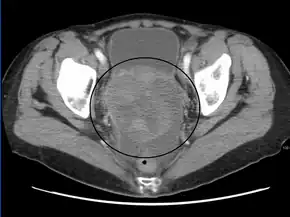

Stage 4 ovarian cancer